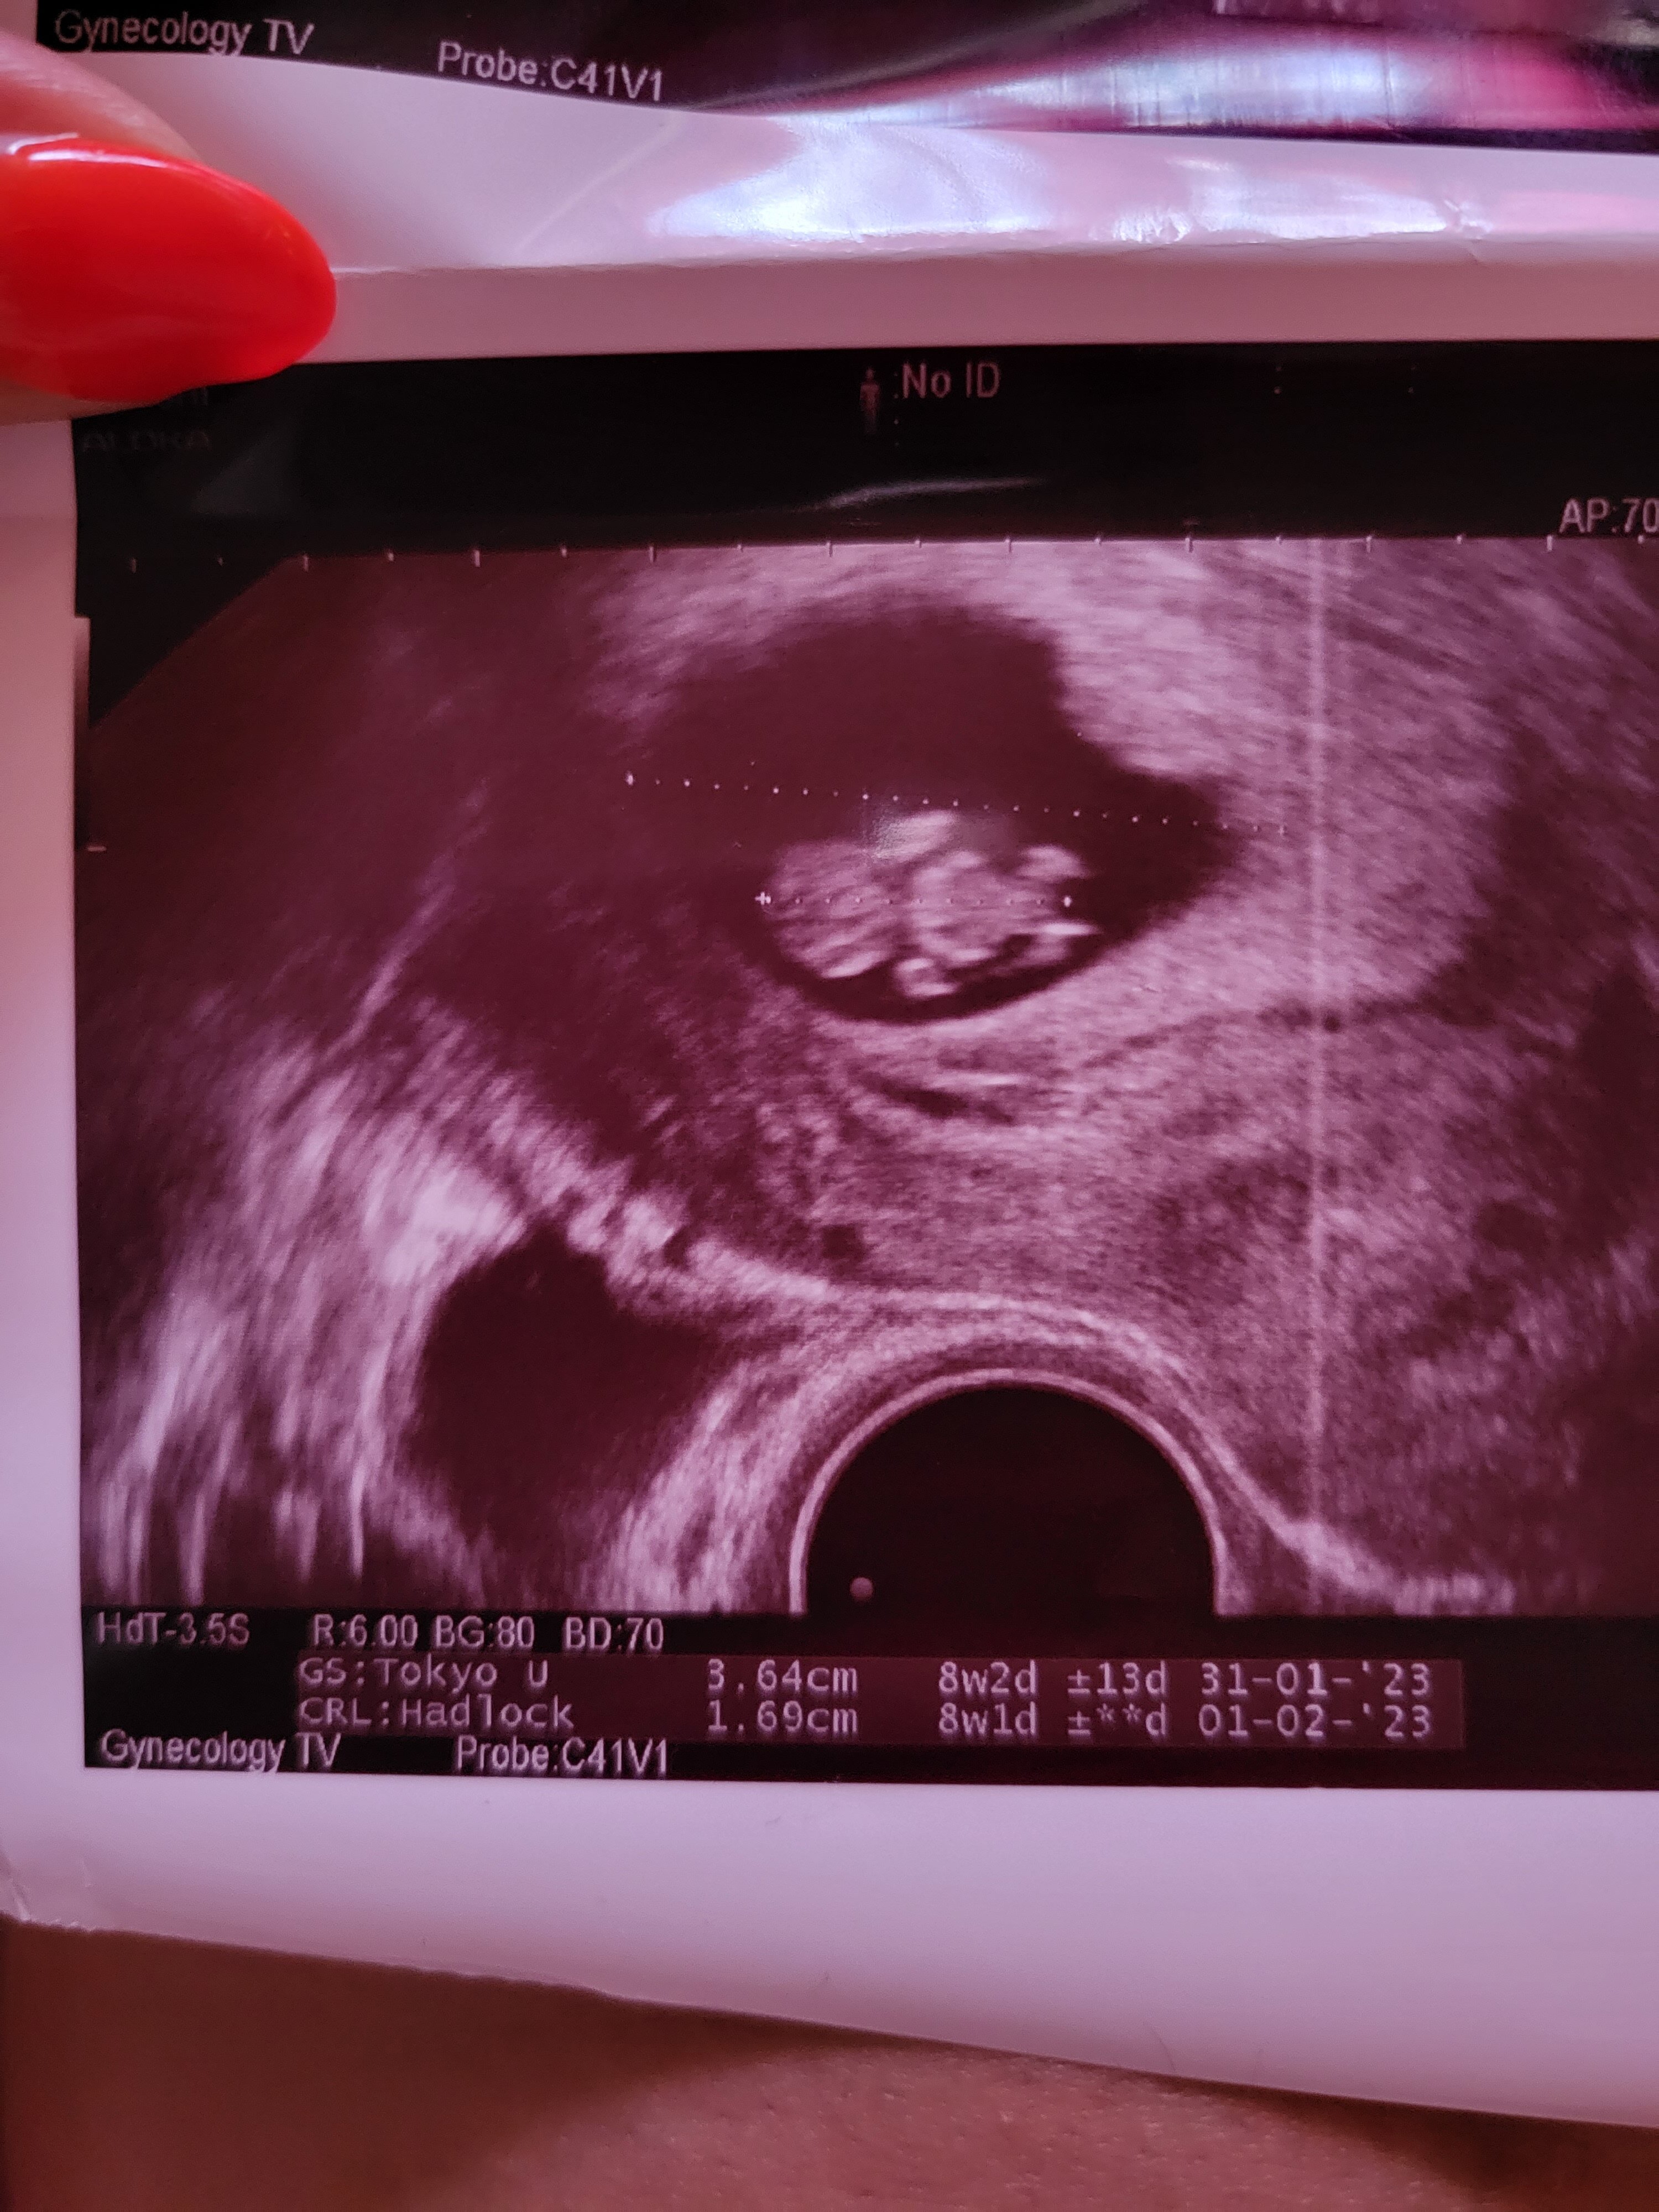

Jestem Jula , mama 9 letniej Leny i 6.5 letniej Igi :) termin na 31.01 a młodsza córkę urodziłam 30.01 więc może się uda wstrzelić aby były wspólne urodziny. Po pozytywnym teście nie robiłam żadnych badań krwi tylko czekałam na 8 tydzień i poszłam na wizytę. We czwartek zobaczyłam małego człowieczka z bijącym serduszkiem. 💗💗. Mimo wszystko żaden lekarz nie chce prowadzić mojej ciąży że względu na moje choroby i każdy odsyła do Matki Polki.